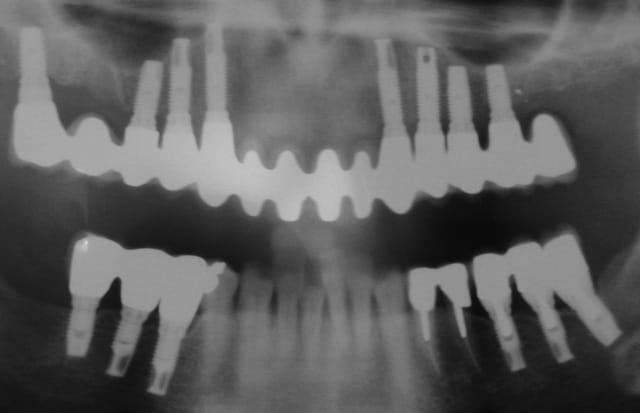

>j'ai oublié les images...

Södeb pano24.01 - Eugenol

Söd def  copie cj2jza - Eugenol